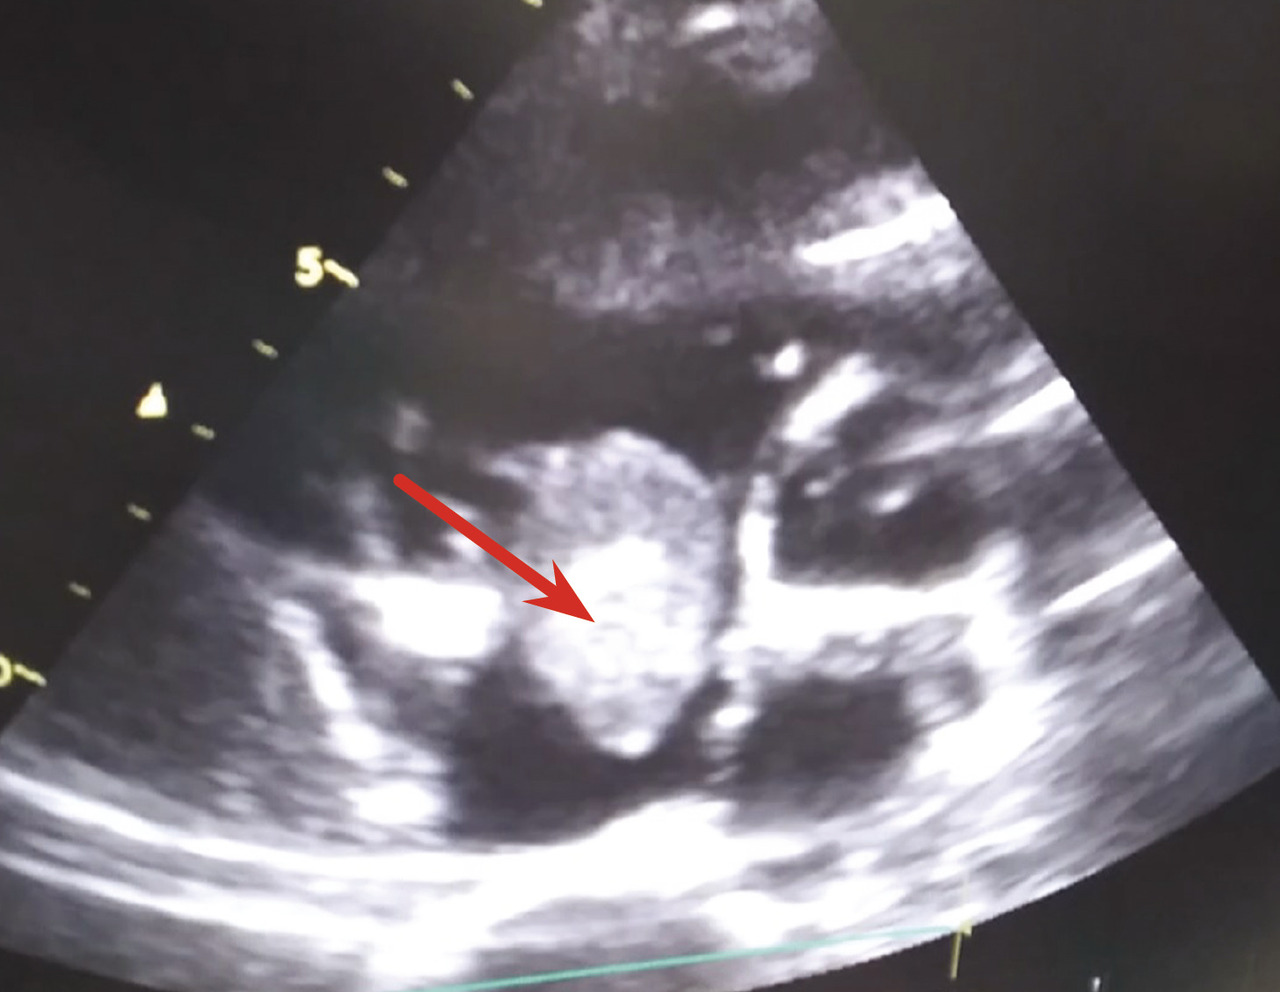

Un angioscanner thoracique objective une embolie pulmonaire bilatérale (fig. 1 ) et une échocardiographie transthoracique montre une masse d’échogénicité hétérogène polylobée mobile mesurant 30 mm, au niveau de l’oreillette droite attachée au septum interatrial (fig. 2 ). L’examen histologique confirme qu’il s’agit d’un thrombus (fig. 3 ). Face à ces résultats, l’indication chirurgicale est posée. Le patient est mis sous traitement anticoagulant, corticothérapie générale et immunosuppresseur.

Un angioscanner thoracique objective une embolie pulmonaire bilatérale (